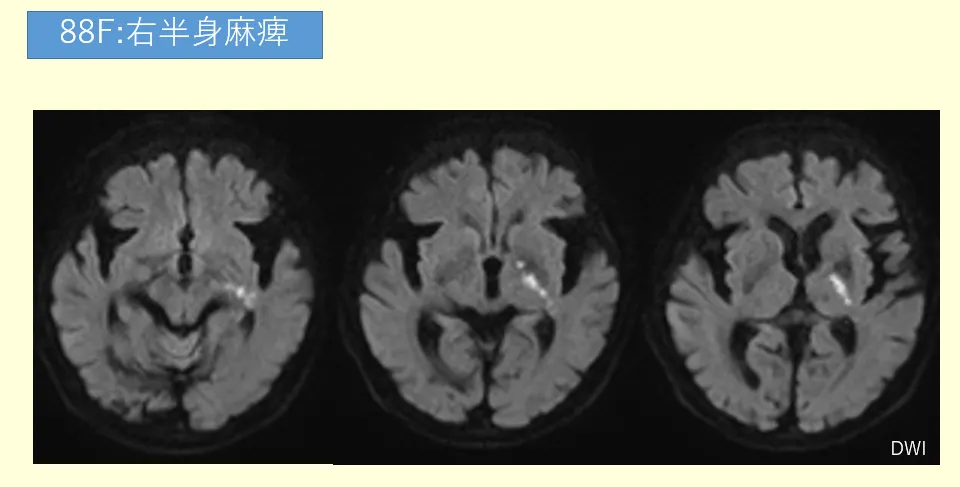

症例:78歳女性、右上下肢の脱力を主訴に来院。

左の基底核に拡散強調画像高信号域があります。梗塞巣は非常に小さく、ラクナ梗塞のように見えます。しかし、待ってください。スライスを上下に送ると、梗塞巣がずっと続いていきます…1枚、2枚…6枚にもわたって縦に長い。これは典型的なラクナ梗塞ではありません。続いて中大脳動脈(MCA)の閉塞を予測してMRAを立ち上げますが…結果は、異常なし。血管は驚くほどきれいです。心原性塞栓症を疑う既往歴もありません。

この症例は、まさにBAD(分子粥腫型脳梗塞)の典型例でした。本記事では、このBADの病態から画像所見、そして私たち放射線技師が現場で実践すべき鑑別診断のポイントまでを徹底解説していきます。